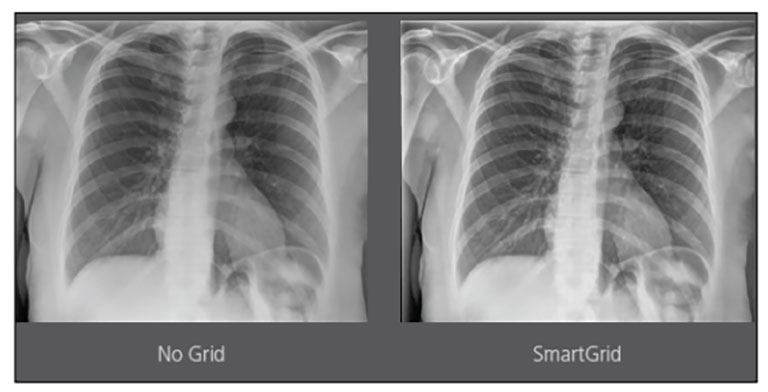

CARESTREAM Image Suite V4 MR11 has set a new standard for workflow efficiency, offering a robust set of features and functionalities to enhance clinical confidence in healthcare professionals. Using an auto-generated companion image from a single exposure, leverage a range of image processing options to increase diagnostic accuracy and enhance patient care.

Our Carestream Focus HD 35/43 Retrofit Detectors, powered by Image Suite Software, are an ideal solution to step up to full digital X-ray for customers who simply cannot compromise on image quality. It seamlessly integrates into existing setups, bringing the power of full digital X-ray with minimal disruption and maximum clarity, along with the following benefits: